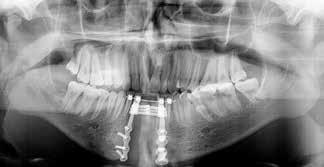

Klik ind på Tandlægebladet.dk og opret en reklamation, så sørger vi for, at bladet lander i din postkasse.

Klik ind på Tandlægebladet.dk og vælg om os

BAGGRUND – Transverselle okklusionsafvigelser kombineret med en vækstbetinget kæbedeformitet korrigeres sædvanligvis ved en sektioneret Le Fort 1-osteotomi eller kirurgisk assisteret ganeekspansion. Ved ekstreme transverselle skeletale diskrepanser mellem maksillen og mandiblen kan der være indikation for transversel udvidelse af mandiblen ved hjælp af mandibulær midtlinjeosteotomi eller mandibulær midtlinjedistraktionsosteogenese.

PATIENTTILFÆLDE – En 15-årig dreng med infantil autisme blev henvist fra Hjørring Kommunes Tandpleje til Kæbekirurgisk Afdeling, Aalborg Universitetshospital, for ortodontisk-kirurgisk behandling af et stort horisontalt maksillært overbid uden kontakt på nogen af tænderne. Den vækstbetingede kæbedeformitet blev korrigeret ved hjælp af ortodonti og mandibulær midtlinjedistraktionsosteogenese efterfulgt af en sektioneret Le Fort I-osteotomi og bilateral sagittal splitosteotomi.

KONKLUSION – Mandibulær midtlinjedistraktionsosteogenese er en forudsigelig behandlingsmodalitet til transversel udvidelse af mandiblen. Imidlertid er behandlingen forbundet med en betydelig risiko for recidiv samt biologiske og tekniske komplikationer, hvorfor mandibulær midtlinjedistraktionsosteogenese udelukkende anbefales til korrektion af ekstreme vækstbetingede transverselle okklusionsafvigelser.

EMNEORD Jaw abnormalities | malocclusion | orthodontics | orthognathic surgery

PERNILLE SAGBAKKEN, tandlæge, Odontologisk Institut, Det Sundhedsvidenskabelige Fakultet, Københavns Universitet

ANNETTE DALGAARD KJELLERUP, specialtandlæge i ortodonti, Kæbekirurgisk Afdeling, Aalborg Universitetshospital